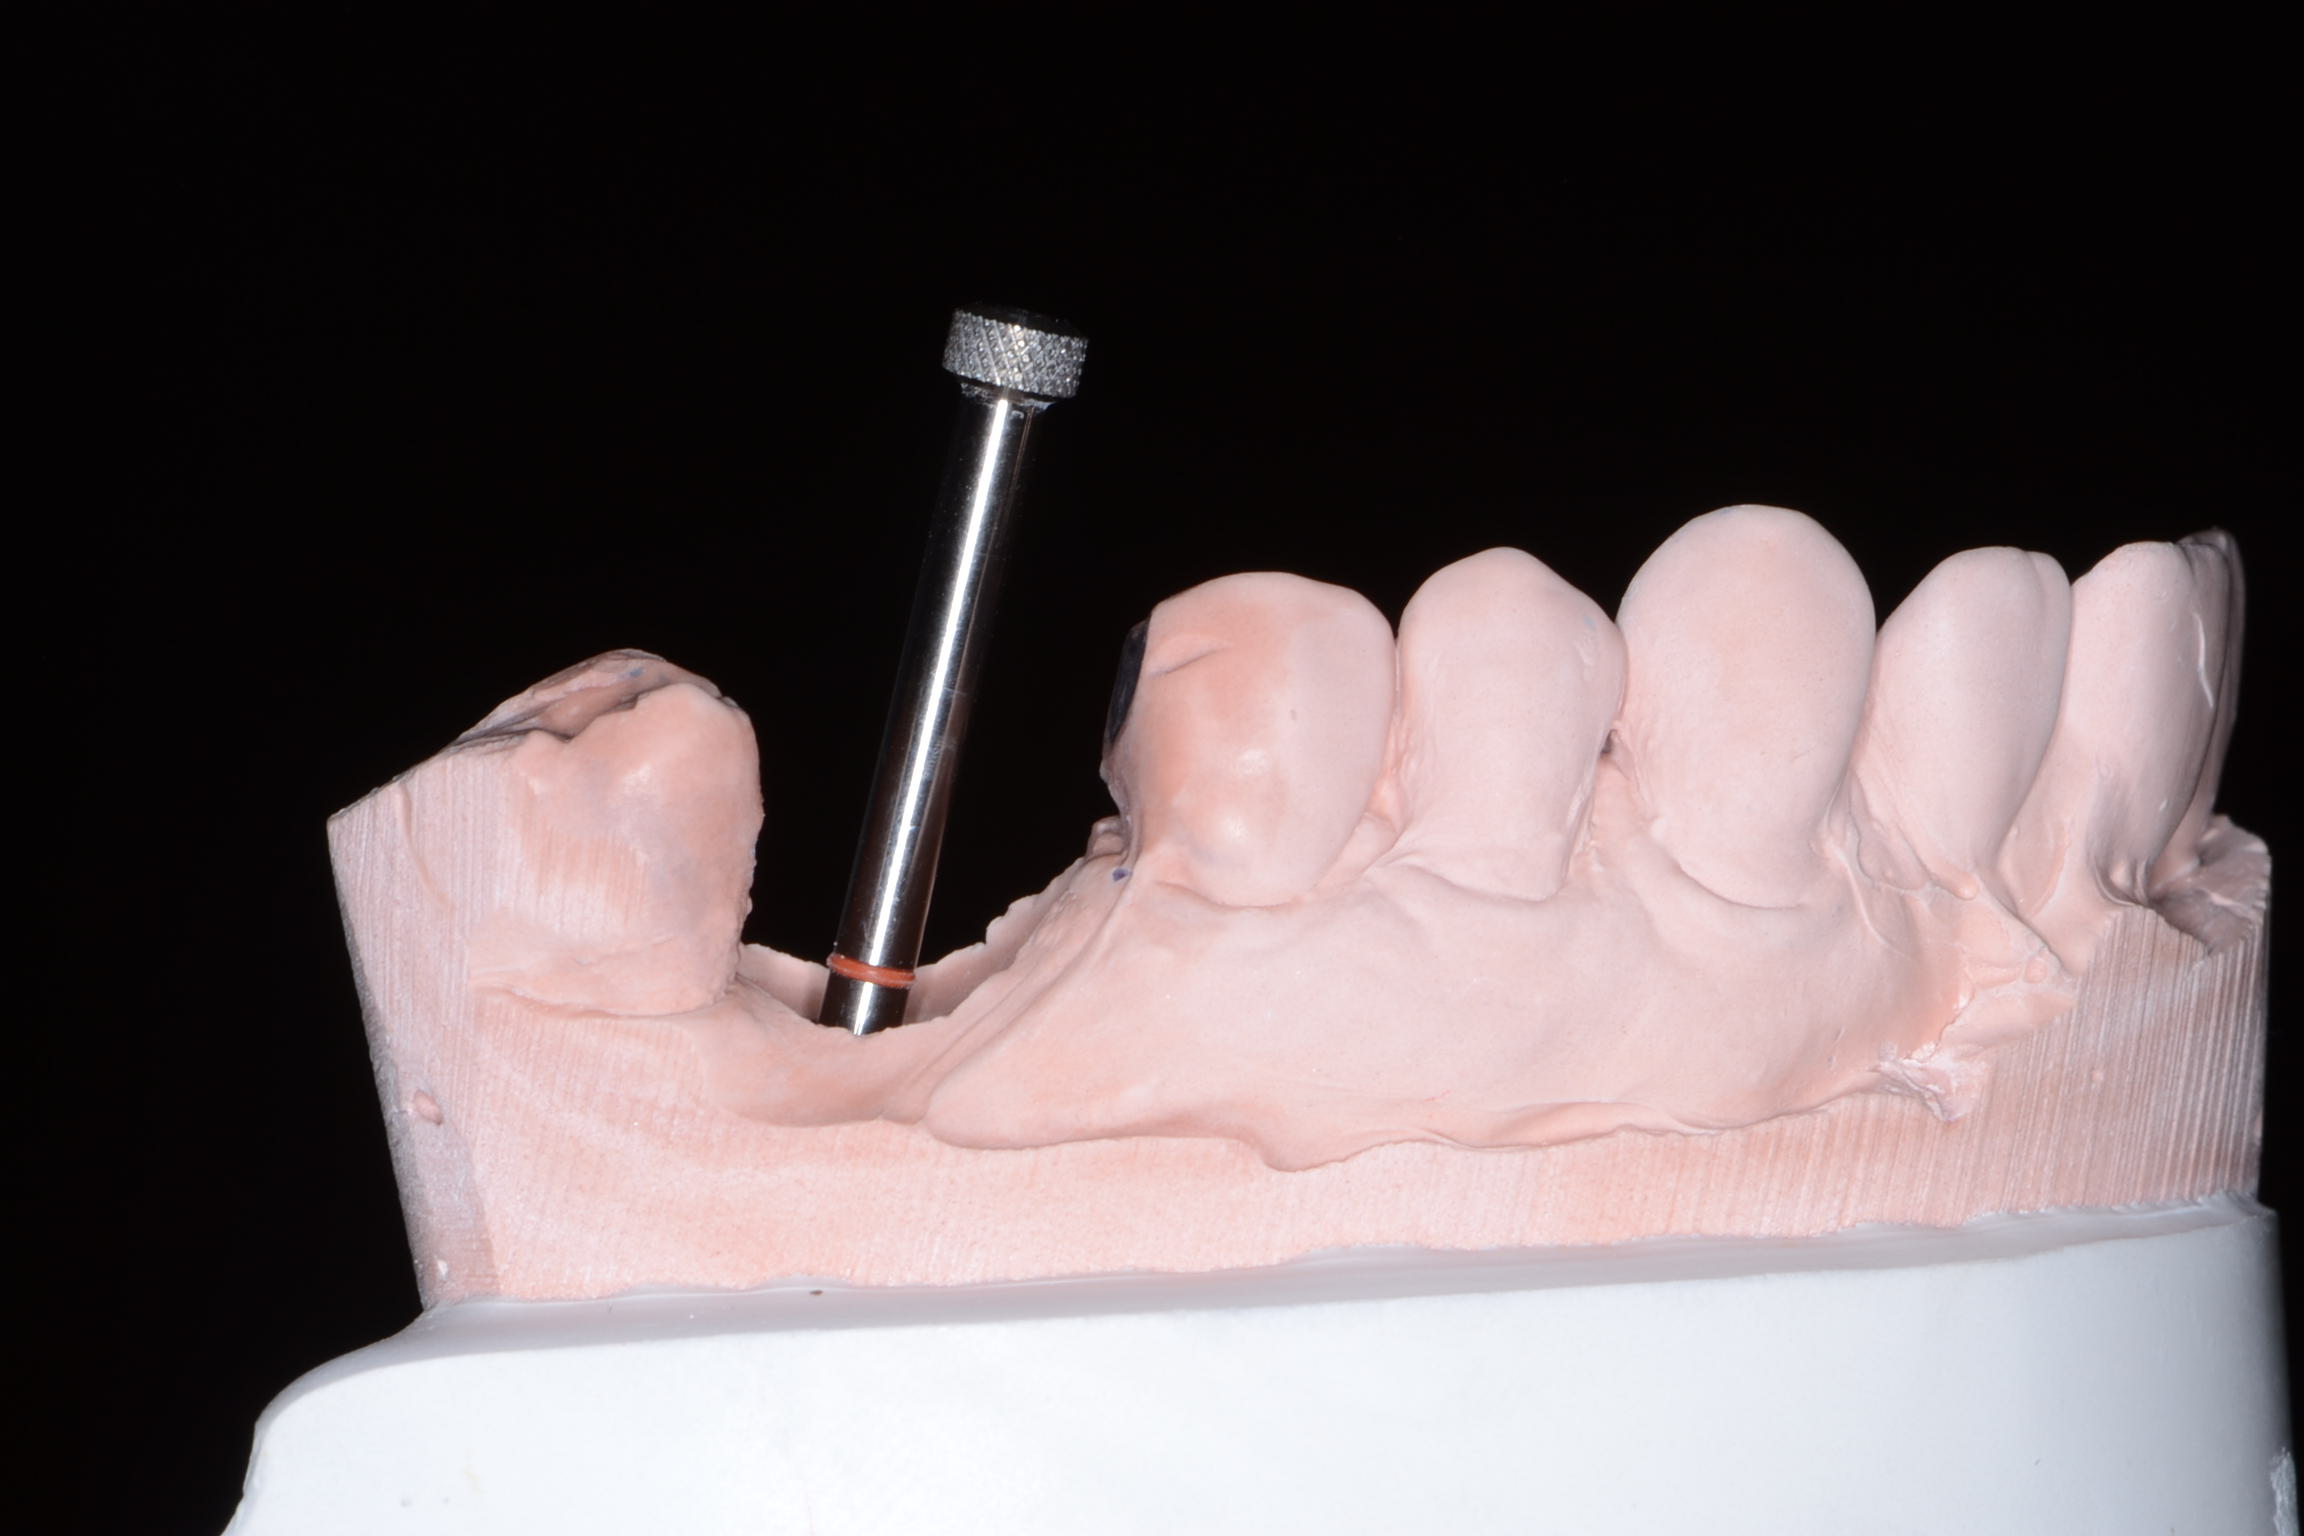

Fig 7. Ill-fitting milled abutment obtained from a third-party vendor and not from the manufacturer.

Figure 7